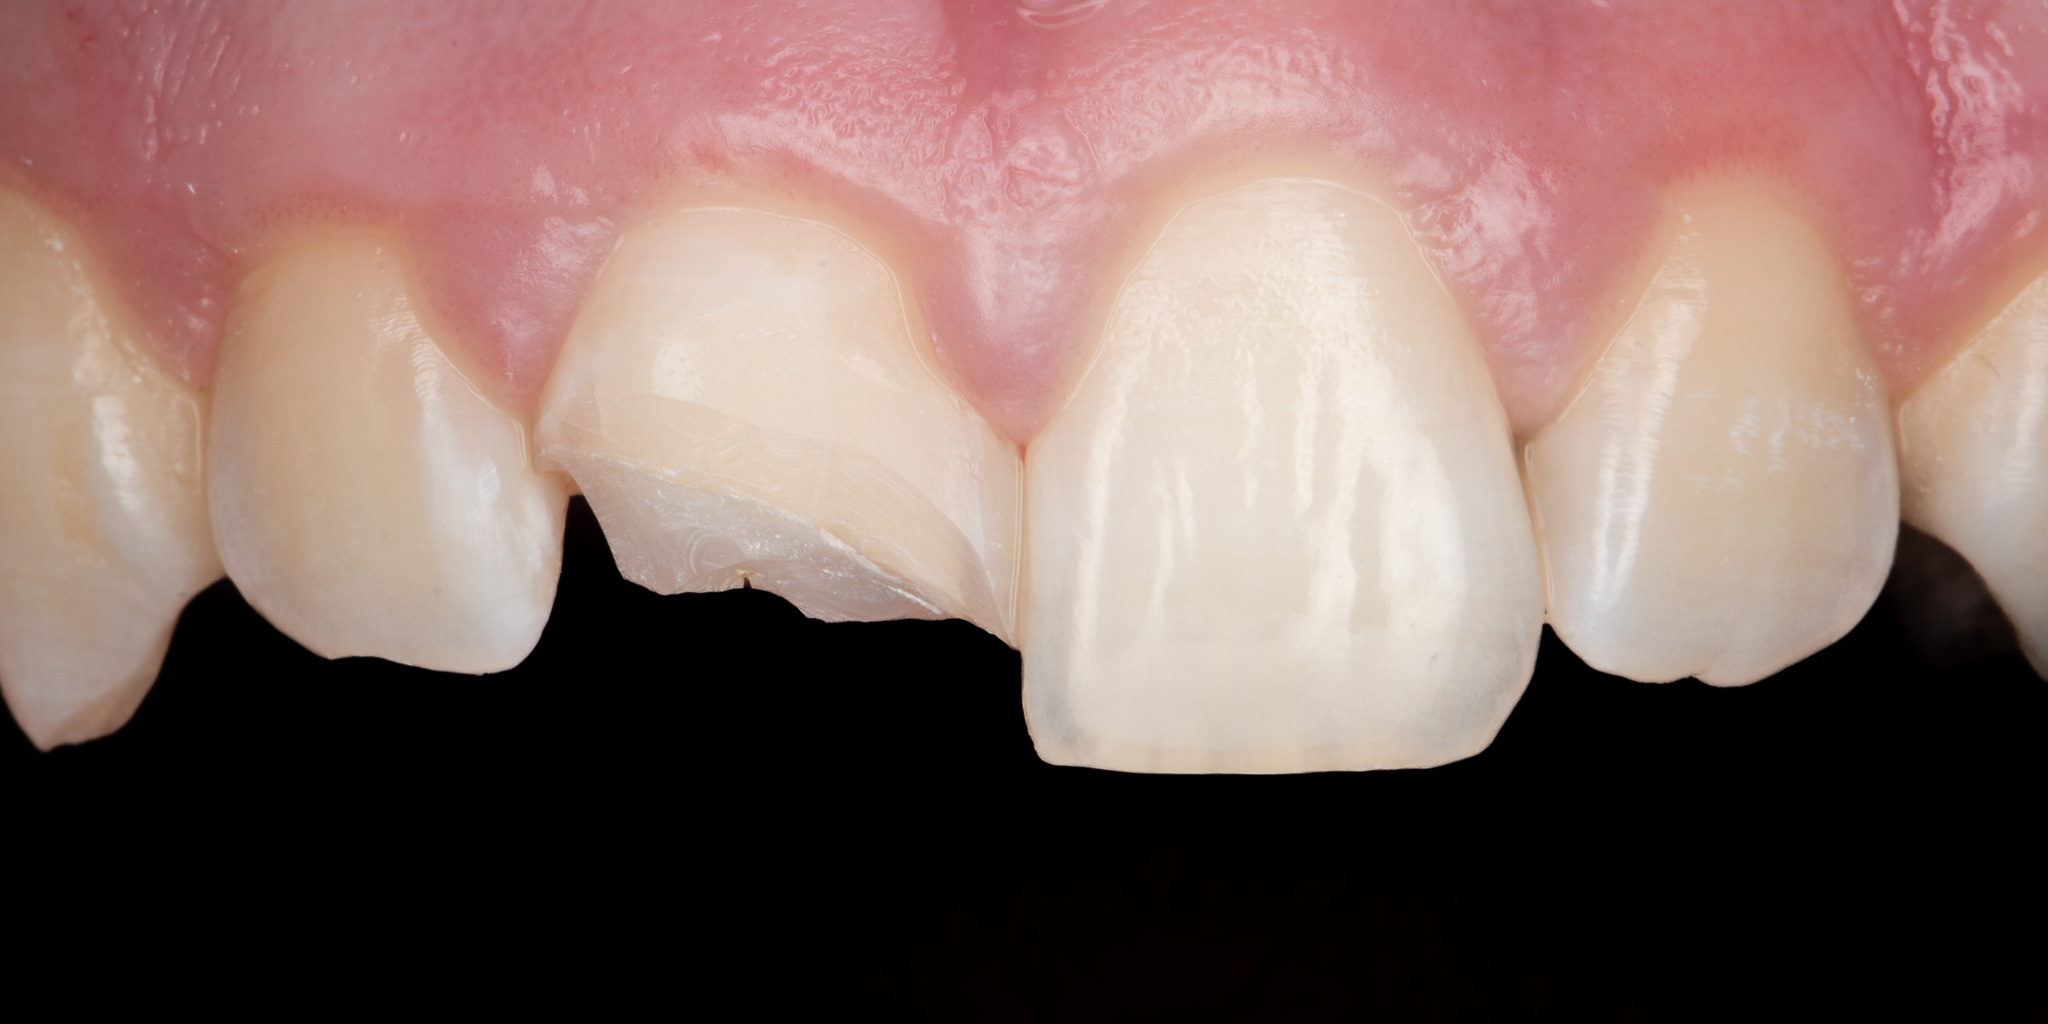

Pacjent zgłosił się podając złamie prawego siekacza centralnego (jedynki) w wyniku urazu. Wykonano estetyczną odbudowę biomimetyczną materiałem kompozytowym 3M™ Filtek™ Universal zapewniającym wysoką estetykę a także podniesioną odporność mechaniczną w porównaniu do konwencjonalnych wypełnień.